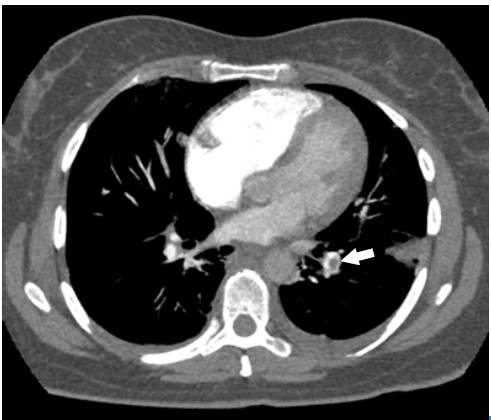

The Wells scale was applied, finding a high probability for pulmonary thromboembolism. Anticoagulation was initiated with low molecular weight heparin (enoxaparin) at a dose of 1 mg/kg every 12 hours, and a computed axial angiography (AngioCAT) of the chest was performed, confirming the diagnostic suspicion by reporting pulmonary artery obstruction in the trunk of the lower left basal segment (Figure 2).

Angiotomography of the chest. Axial plane. Pulmonary embolism, filling defect in the shape of a life preserver sign (arrow).

Fig 2: Angiotomography of the chest. Axial plane. Pulmonary embolism, filling defect in the shape of a life preserver sign (arrow).

Angiotomography of the chest. Coronal plane. Pulmonary embolism, filling defect configuring the railway track sign (arrow), left basal consolidation of the pleural base and air bronchogram corresponding to pulmonary infarction (star).

Fig 3: Angiotomography of the chest. Coronal plane. Pulmonary embolism, filling defect configuring the railway track sign (arrow), left basal consolidation of the pleural base and air bronchogram corresponding to pulmonary infarction (star).